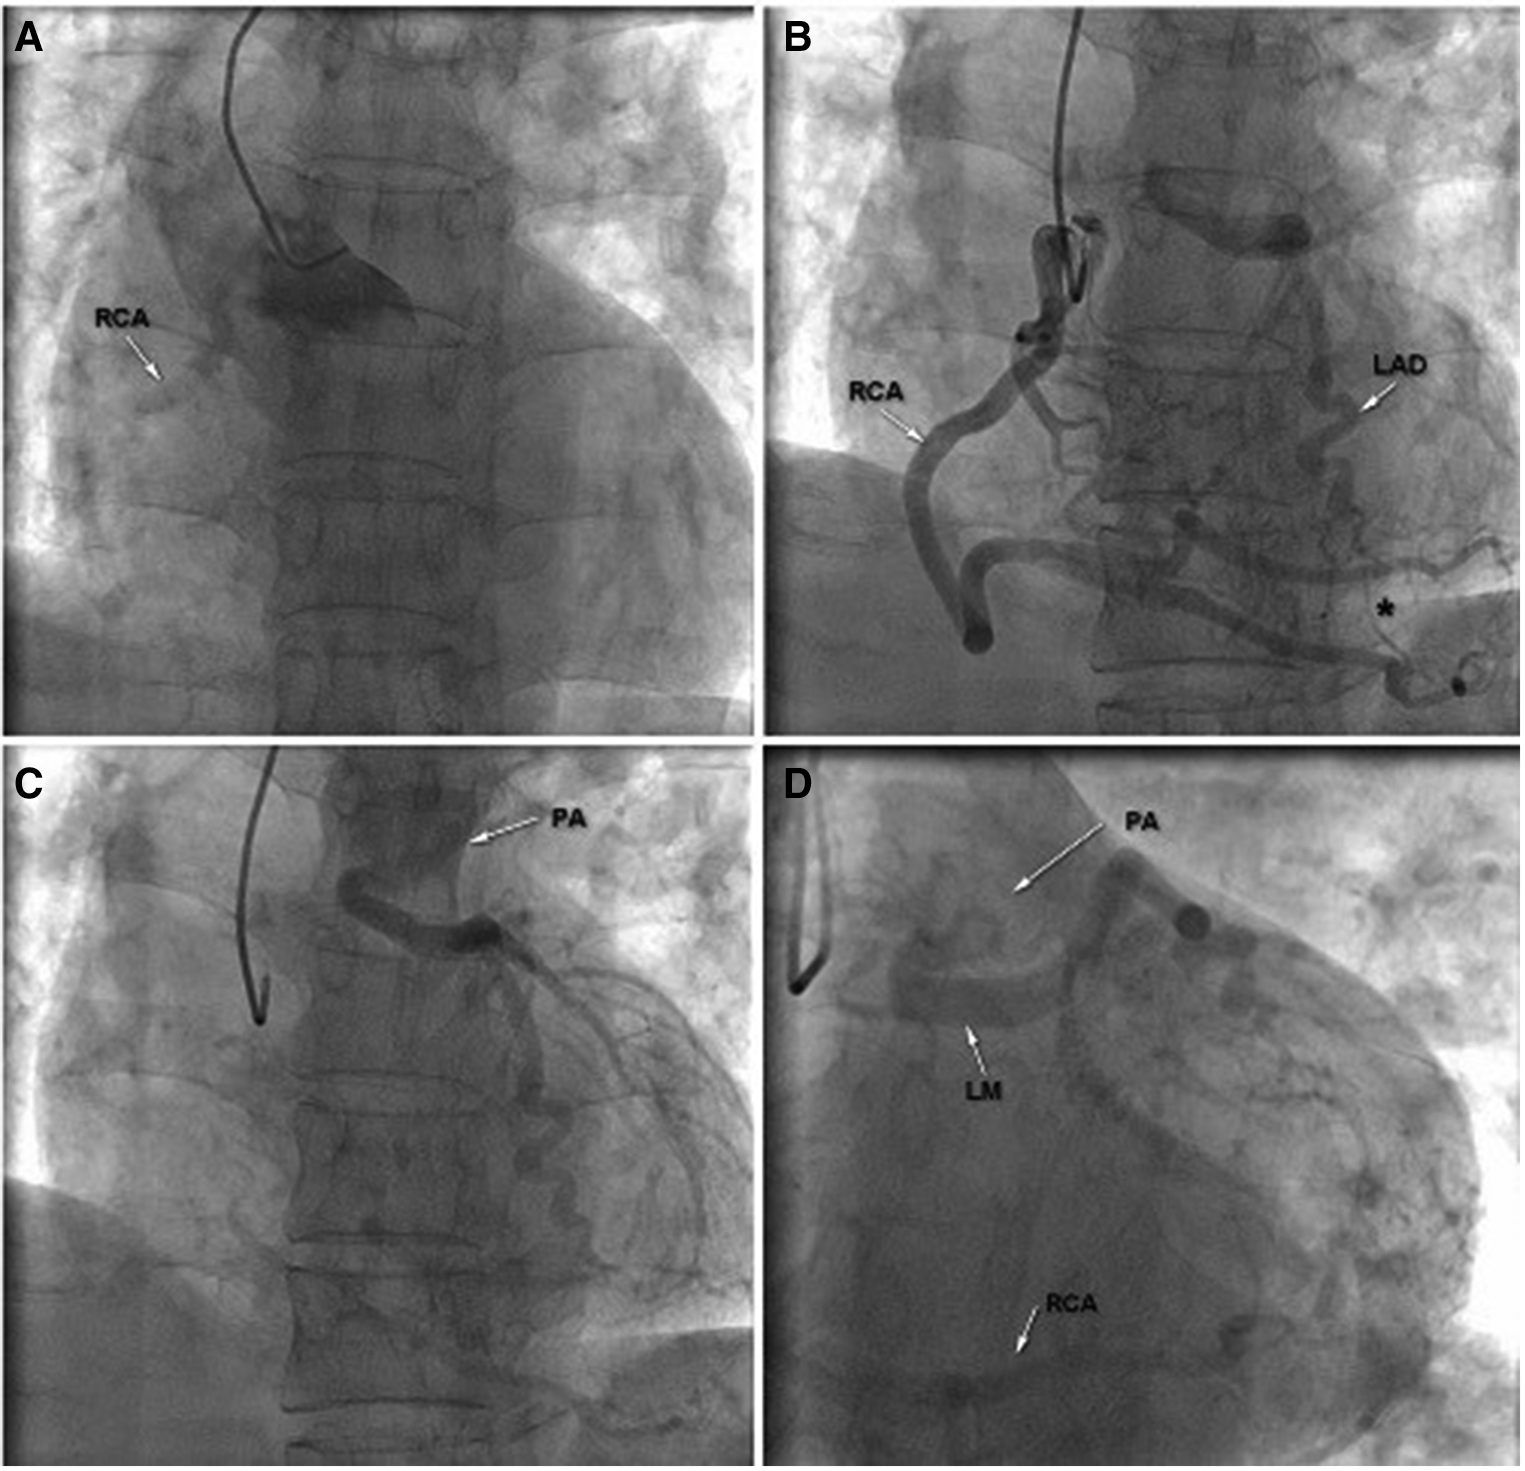

The patient was then transferred to the cardiac catheterization laboratory for further evaluation. Multiple attempts failed to engage the left main coronary artery (LMCA), but the transradial CAG revealed an extremely large and tortuous RCA arising from the right coronary cusp (RCC) with significant collateral flow from RCA to LCA. The blood flow terminated in the pulmonary artery through the LCA, and delayed enhanced-imaging demonstrated the LCA filling via extensive intercoronary collateral circulation, which supported the diagnosis of ALCAPA (Figures 2A–D and Supplementary Videos S2A,S2B). Surgical correction for ALCAPA was planned.

Figure 2

Transradial coronary angiography was performed; however, multiple attempts failed to engage the left main coronary artery (LM) (A); right coronary angiography revealed an extremely large and tortuous RCA arising from the RCC with significant collateral flow from RCA to LCA (B). The blood flow terminated in the pulmonary artery through the LCA and delayed enhanced-imaging demonstrated the LCA filling via extensive intercoronary collateral circulation, which supported the diagnosis of ALCAPA (C,D). LA, left main coronary artery; LAD, left anterior descending; PA, pulmonary artery; RCA, right coronary artery.